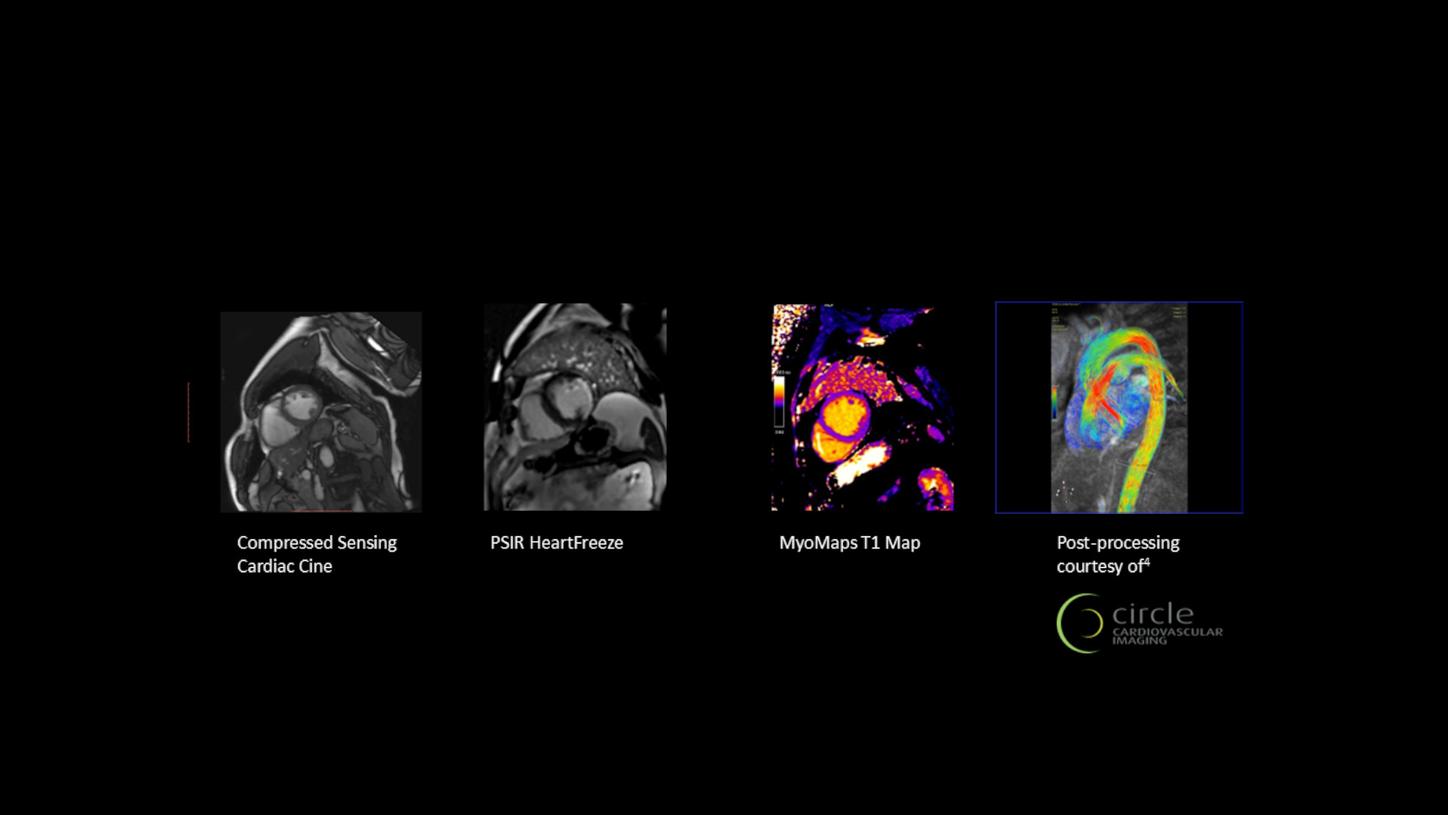

XA Upgrades preview image